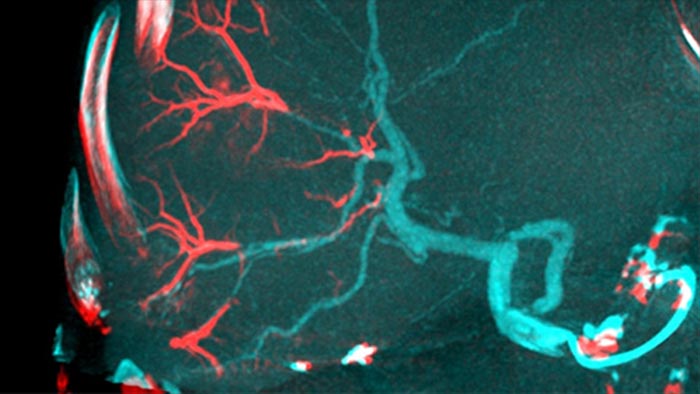

塞栓術後の3D画像収集では、腫瘍内のリオピドールや放射線不透過ビーズなどの塞栓物質の蓄積状態を視覚化できます⁵。

Dual Viewでは、塞栓術前の動脈相3D画像と塞栓術後の画像を同時に表示して、治療エンドポイントを評価できます。